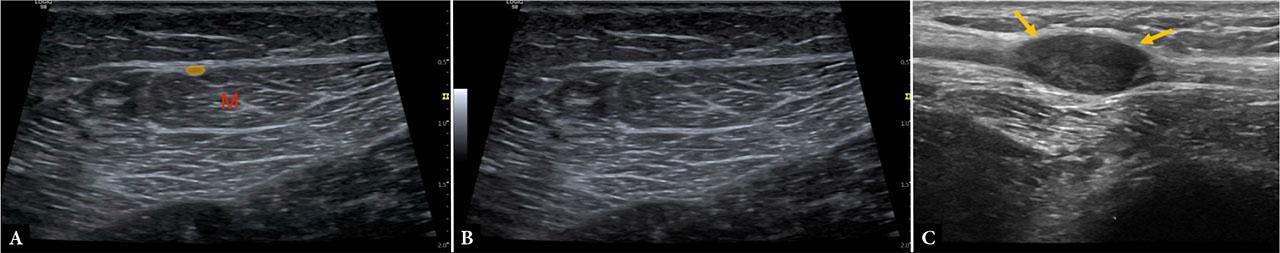

The superficial peroneal nerve arises from the common peroneal nerve, becoming superficial in the distal third of the leg before dividing into dorsal cutaneous branches. It is visualized as it emerges between the peroneus longus and brevis muscles and pierces the crural fascia. Variations in the fascial exit point are common and may predispose to entrapment neuropathy, particularly in athletes and patients with chronic ankle instability. Ultrasound is valuable both for diagnosis – demonstrating focal nerve enlargement or hypoechogenicity at the fascial penetration site – and for guiding therapeutic hydrodissection or perineural injections(2,22,23,24) (Fig. 13).

Images A and B demonstrate the normal superficial peroneal nerve (yellow) in the mid-lower leg as it pierces the lateral muscular septum, with underlying lateral muscle bellies (M). Image C shows a peripheral nerve sheath tumor involving the superficial peroneal nerve (arrows)